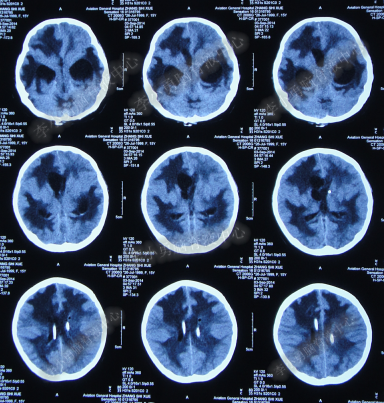

第3次手术右侧脑室外引流术后1个月时间内,脑积水仍没有得到控制,再给予腰大池引流,期间多次试图拔除右侧脑室外引流管(多次调高脑室外引流管的高度),但因患者意识变差,而无法拔除引流管,给予拔除腰大池引流,治疗期间曾多次查头部CT均示脑积水仍无改善(图-20、图-21、图-22、图-23)。

图-20:2014年7月24日头部CT

图-21:2014年7月29日头部CT

图-22:2014年8月4日头部CT

图-23:2014年8月15日头部CT